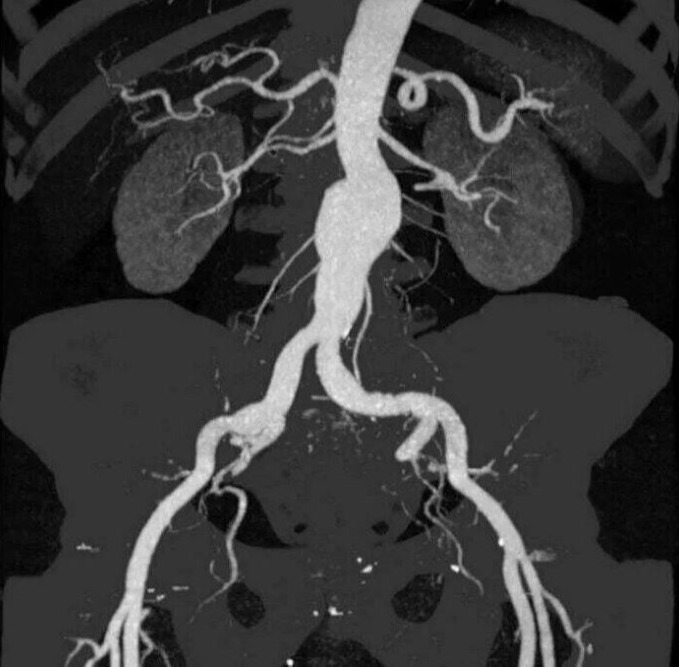

Διαγνωστικές εξετάσεις κοιλιακής αορτής και σπλαχνικών αρτηριών

Οι διαγνωστικές εξετάσεις για την αξιολόγηση της κοιλιακής αορτής και των σπλαχνικών αρτηριών μπορεί να περιλαμβάνουν τις εξής μεθόδους:

Αγγειογραφία της Κοιλιακής Αορτής και των Σπλαχνικών Αρτηριών (Celiac Artery Angiography): Αυτή η εξέταση χρησιμοποιείται για να αξιολογήσει την κατάσταση της κοιλιακής αορτής και των αρτηριών που εξυπηρετούν τα σπλάχνα. Συνήθως, περιλαμβάνει τη χρήση χρωματιστικού υγρού για εμφανή οπτικοποίηση των αγγείων στις ακτινογραφίες.

Σπιράλ Υπολογιστική Τομογραφία (CT Angiography - CTA): Η CTA είναι μια μέθοδος εικονογράφησης που χρησιμοποιεί την τεχνολογία της υπολογιστικής τομογραφίας για τη δημιουργία λεπτομερών εικόνων των αγγείων. Συνήθως, περιλαμβάνει και τη χρήση χρωματιστικού υγρού για καλύτερη οπτικοποίηση των αγγείων.

Μαγνητική Αξονική Τομογραφία (Magnetic Resonance Angiography - MRA): Η MRA είναι μια μέθοδος που χρησιμοποιεί το μαγνητικό πεδίο για τη δημιουργία εικόνων των αγγείων. Συνήθως, δεν απαιτεί τη χρήση χρωματιστικού υγρού.

Δοπλερογραφία των Σπλαχνικών Αρτηριών (Doppler Ultrasound of Splanchnic Arteries): Η δοπλερογραφία χρησιμοποιείται για τον έλεγχο της ροής του αίματος στις σπλαχνικές αρτηρίες και την ανίχνευση πιθανών προβλημάτων, όπως στενώσεις ή ανευρύσματα.

Ο ιατρός θα επιλέξει την κατάλληλη μέθοδο ανάλογα με τα συμπτώματα, την ιατρική ιστορία και τις ανάγκες του ασθενούς.